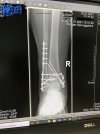

ich habe mir am 31.01. eine trimalleoläre Sprunggelenksfraktur (Weber C) mit Syndesmoseriss zugezogen, die drei Tage später operiert wurde. Wieder drei Tage nach der OP war ich daheim. Ich lebe allein mit meiner 3-jährigen Tochter. Die nächsten Wochen waren unschön. Unter anderem habe ich meinen neuen Job verloren (Probezeit) und seit erstem März keine Krankenversicherung und auch keinerlei Einkommen. Ansonsten aber medizinisch gesehen alles gut: Ich hab es geschafft, nie auf den verletzten Fuß zu treten, hatte durchgängig Lymphdrainage und der Chirurg meinte anhand der Röntgenbilder drei Wochen postoperativ, es sei alles super zusammengewachsen.

Gestern habe ich endlich meine Stellschraube entfernt bekommen - was übrigens mit der lokalen Betäubung verdammt weh getan hat.

Jetzt darf ich bis zur Schmerzgrenze belasten. Aber wie? Meinen Fuß kriege ich gar nicht neben den anderen auf den Boden. Er steht schräg 30 Zentimeter vor mir. War das bei einem von euch auch so? Ist das nur die steife Achillessehne? Es fühlt sich immer noch alles so blockiert an.